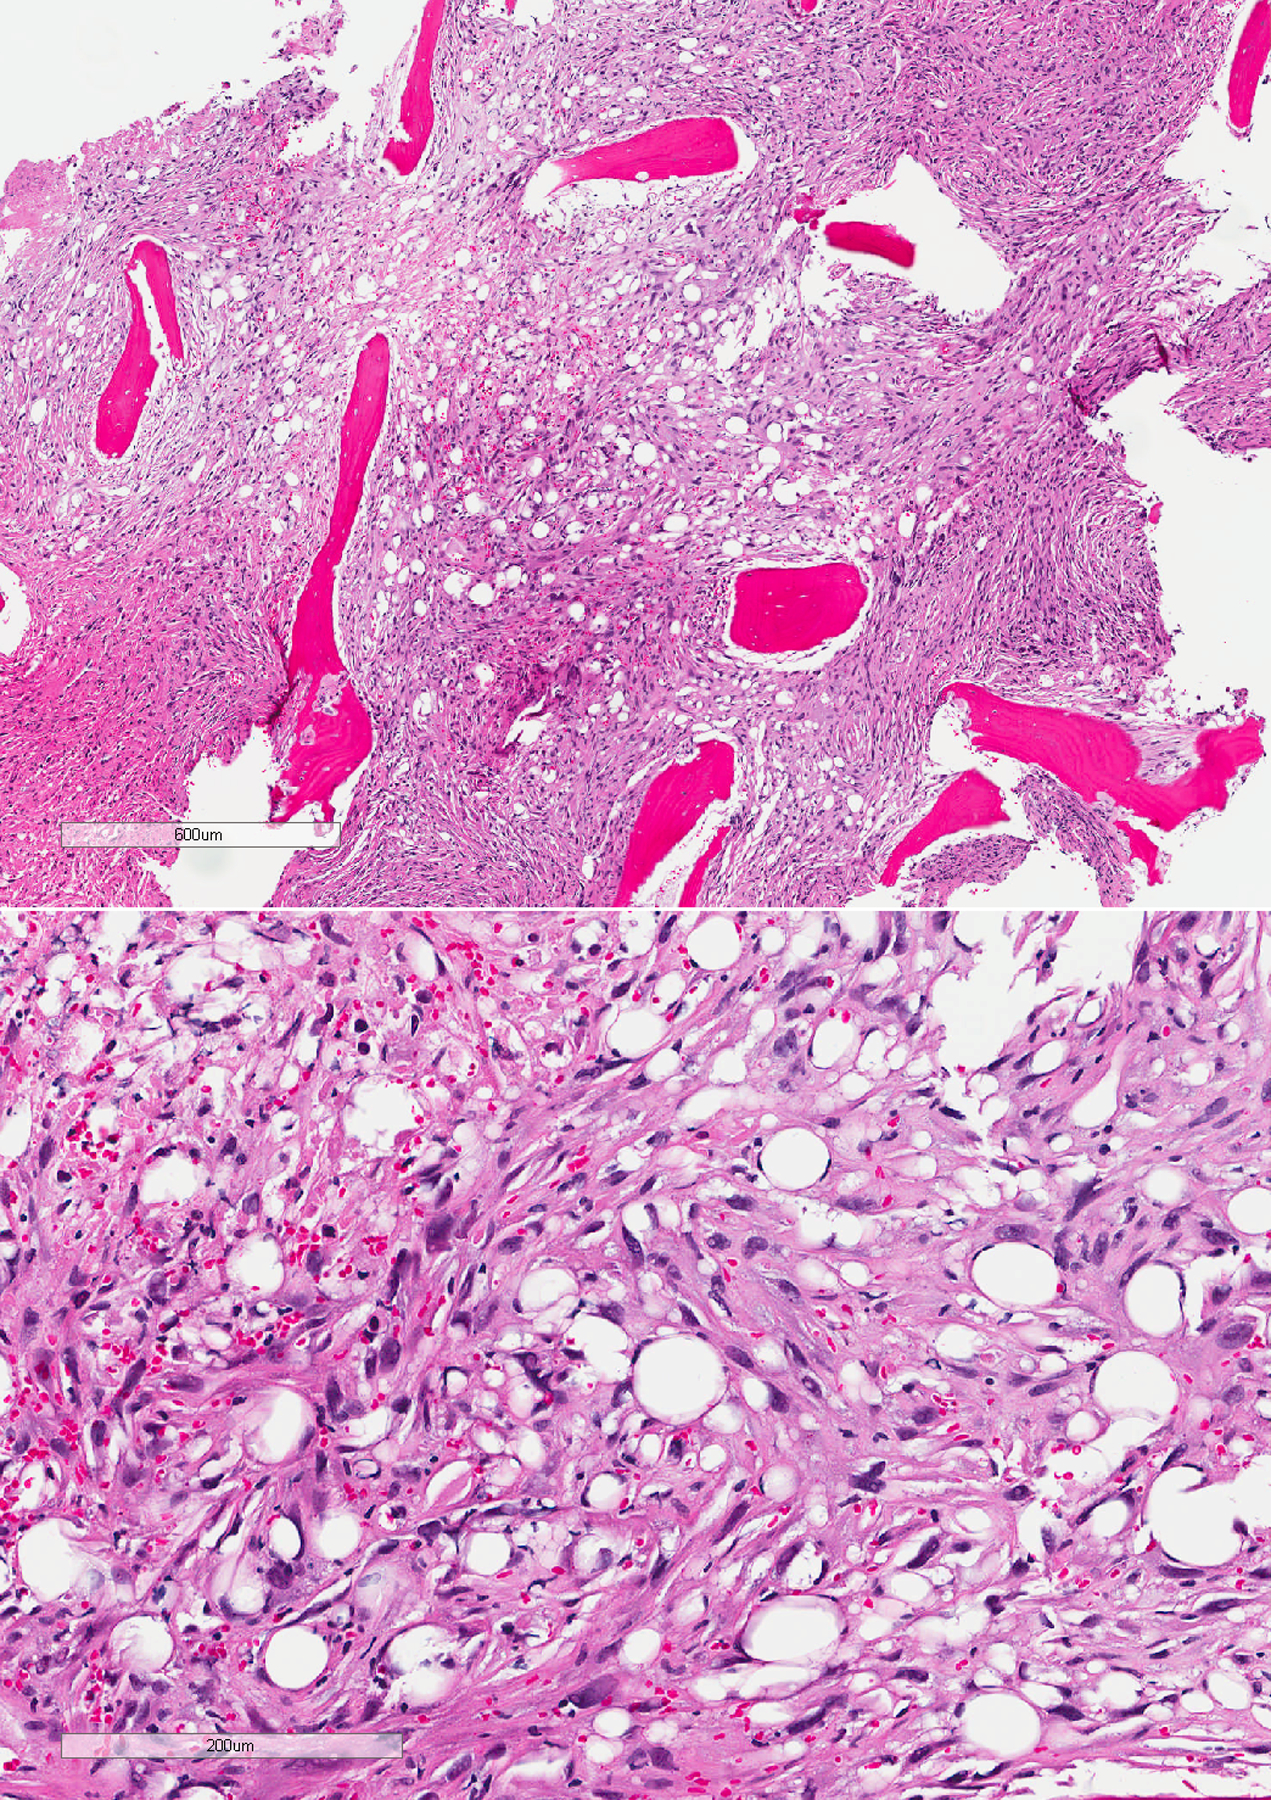

Sarcomatoid mesotheliomas can be challenging to diagnose on small biopsy specimens, where limited material may preclude definitive assessment of invasion and lesional cells can have relatively bland cytology with no mesothelial marker expression. We report a case of a patient who presented with a pleural effusion and had subsequent pleural biopsy that showed a bland, uniform spindle cell proliferation in a mildly myxoid background. There was little if any collagen; no chest wall, soft tissue, or fat; and mesothelial markers were negative. The cells were positive for pancytokeratin and GATA3 by immunohistochemistry, and in situ hybridization showed a "negative" result for homozygous loss of CDKN2A; however, there was partial (heterozygous) loss of one allele. A diagnosis of atypical spindle cell proliferation was made based on these findings. Several months later, the patient had a repeat pleural biopsy that showed spindled cells with more pleomorphism, areas of invasion into the chest wall, and the same partial loss of CDKN2A, consistent with a sarcomatoid mesothelioma. This case underscores the challenges present on small biopsy specimens, the fact that sarcomatoid mesotheliomas can be relatively bland appearing with focal pleomorphism, and that heterozygous loss of CDKN2A should be considered a positive result indicative of a neoplastic process.